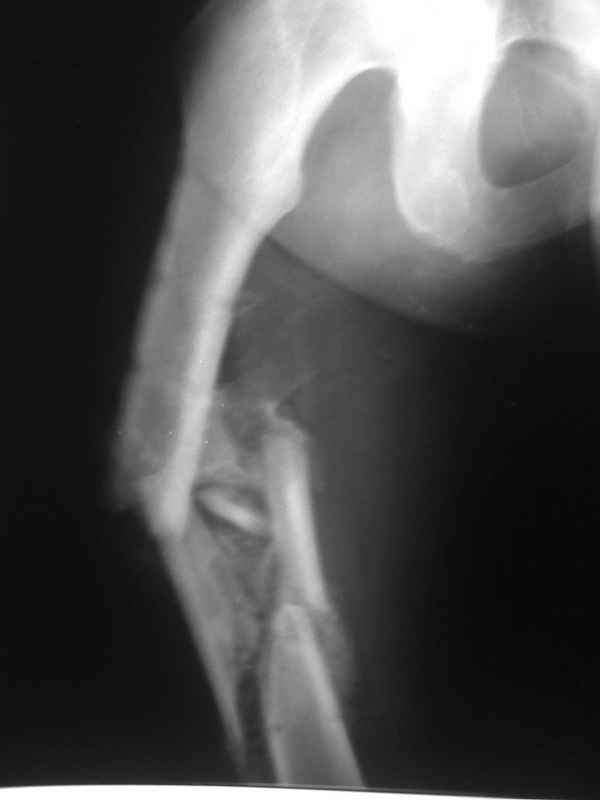

Пациент 39 лет. Травма в ДТП 2.5 месяца назад. Тяжелая сочетанная травма. ЗЧМТ. Тупая травма живота. Разрыв селезенки. Надрывы печени. Перелом бедра. При поступлении лапаротомия. Спленэктомия. Фиксация перелома бедра стержневым аппаратом. в последующем инфаркт мозга на фоне жировой эмболии. длительное нахождение на ИВЛ. Обширный пролежень в области крестца. и т.д.в настоящее время состояние больного стабилизировалось. активизирован на ходунках.имеется деформация бедра, укорочение 10 см. гранулирующий пролежень в области крестца. патологической подвижности в зоне перелома не отмечается.Оптимальные сроки проведения реконструктивной операции на бедре? Сейчас? Или после окончательного сращения?

Конечно, снимки для планирования надо нормальные, не такой огрызок.

Спасибо за снимки. Предложения по тактике прежние.

Попробовать-то можно. И просто руками "об колено", а то и наложить аппарат, приложить флексионные и ротационые усилия прямо за разъединенные секции.

Если уж никак, то сделать чрескожную остеотомию.

Но если картинки недавние, IMHO должно получиться закрыто разобщить.